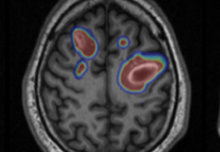

New £10m centre in medical imaging and AI

A new £10m centre, announced today, will help train artificial intelligence to improve diagnosis and care.